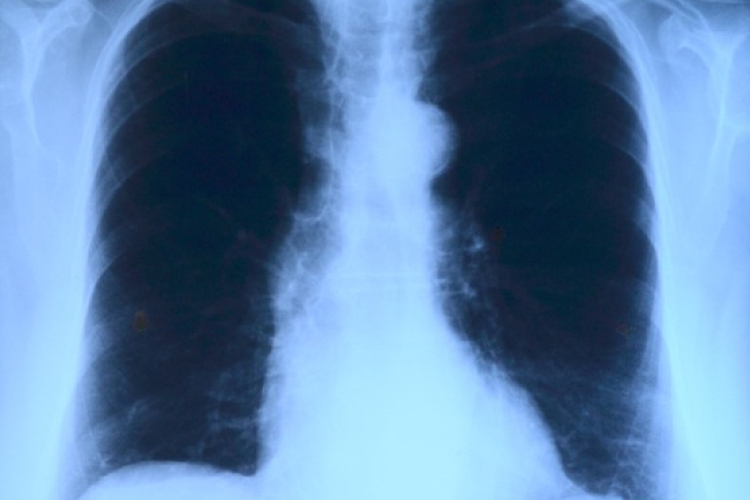

Elvégezték az országban az első tüdőverőér-tágítást

Az országban elsőként a Debreceni Egyetem Klinikai Központjában végeztek tüdőverőér-tágítást - közölte a felsőoktatási intézmény sajtóirodája kedden az MTI-vel.